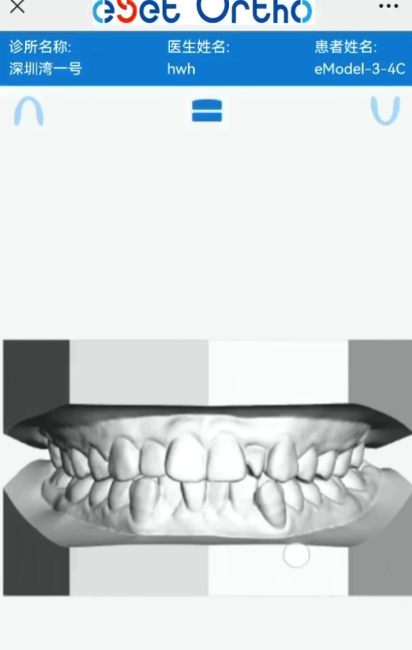

eModel口腔数字模型,安全存储每一颗牙齿的丝米级成长轨迹,让专业医疗级数据成为孩子未来的健康财富!

获模型(口腔诊所数字化口扫)

传云端(三维牙齿健康档案,连接医患的桥梁)

享智能(AI牙齿健康预检,乳牙滞留预警,恒牙萌出先知)

乐分享(零门槛三维查看,一键分享3D模型链接)